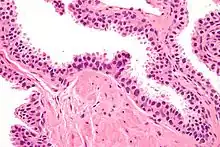

Micrograph showing high-grade prostatic intraepithelial neoplasia. H&E stain. | |

Microscopically, PIN is a collection of irregular, atypical epithelial cells. The architecture of the glands and ducts remains normal. The epithelial cells proliferate and crowding results in a pseudo-multilayer appearance. They remain fully contained within a prostate acinus (the berry-shaped termination of a gland, where the secretion is produced) or duct. The latter can be demonstrated with special staining techniques (immunohistochemistry for cytokeratins) to identify the basal cells forming the supporting layer of the acinus. In prostate cancer, the abnormal cells spread beyond the boundaries of the acinus and form clusters without basal cells. In HGPIN, the basal cell layer is disrupted but present. PIN is primarily found in the peripheral zone of the prostate (75-80%), rarely in the transition zone (10-15%) and very rarely in the central zone (5%), a distribution that parallels the zonal distribution for prostate carcinoma.[7]